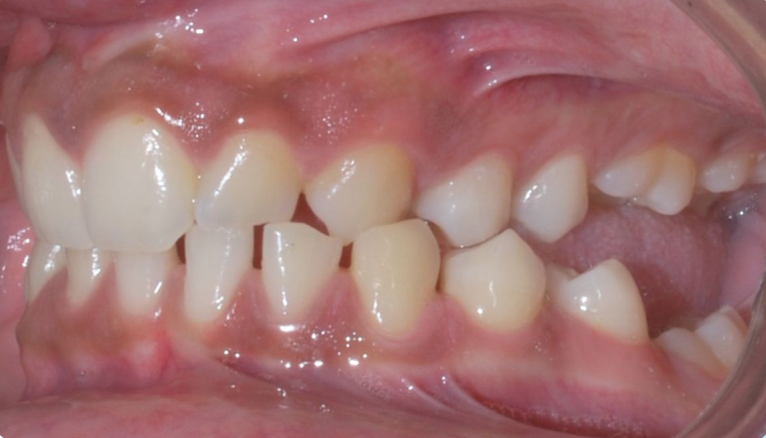

- Class I Malocclusion.

- Class II Malocclusion.

- Class III Malocclusion.

Occlusion And Malocclusion: